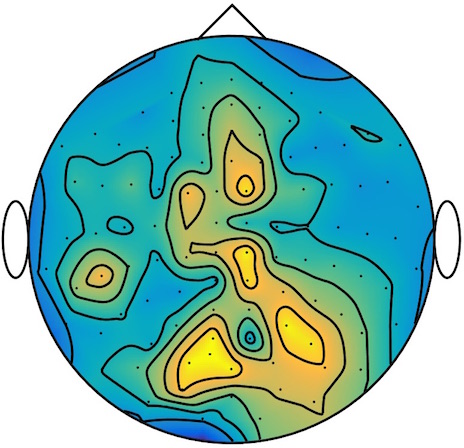

We applied our method to a magnetoencephalography (MEG) dataset. In this setup, brain activity of a subject is recorded (Elekta Neuromag, 306 sensors of which 204 planar gradiometers and 102 magnetometers, sampling frequency 1000Hz) while the subject reacted to the presentation of a target stimulus by pressing either the left or the right button.

Data is preprocessed applying signal space separation correction, interpolation of noisy sensors, and realignment of data into a subject-specific head position (MaxFilter, Elekta Neuromag). The signal was then filtered (low pass 40HZ), and artifacts such as blinks and heartbeats removed thanks to Signal-Space Projection using the Brainstorm software222http://neuroimage.usc.edu/brainstorm. The samples we used for our barycenter computations are an average of the norm of the two gradiometers for each channel from stimulation onto 50ms and the classes were left or right button.

| Class 1 | Class 2 | ||||||

|

|

|

|

|

|

|

|

| Sample 1 | Sample 2 | Sample 3 | Mean | Sample 1 | Sample 2 | Sample 3 | Mean |

|

|

|

|

|

|

|

|

This results in two classes of recordings, one for each pressed button. We aim at computing a representative activity map for each class using Wasserstein barycenters. For each class we have recordings each having samples located on the vertices of an hexahedral mesh of a hemisphere (corresponding to a MEG recording helmet). These recorded values are positive by construction, and we rescale them linearly to impose . Figure 6, top row, shows some samples from this dataset, displayed using interpolated colors as well as iso-level curves. The black dots represent the position of the electrodes on the half-sphere of the helmet, flattened on a 2-D disk.

We computed TV-regularized barycenters independently for each class by solving (16) with the TV regularization using the projected gradient descent method (22). We used a squared Euclidean metric (24) on the flattened hemisphere. Since the data is defined on an irregular graph, instead of (23), we use a graph-based discrete gradient. We denote the graph which connects neighboring electrodes. The gradient operator on the graph is

The total variation on this graph is then obtained by using , the norm, i.e. we use in (23).

Figure 6 compares the naive barycenters (i.e. the usual mean), barycenters obtained without regularization (i.e. ) and barycenters computed with an increasing regularization strength . The input histograms being very noisy, the use of regularization is important to make the area of significant activity emerge from the noise. The use of a TV regularization helps to keep a sharp transition between active and non-active regions.